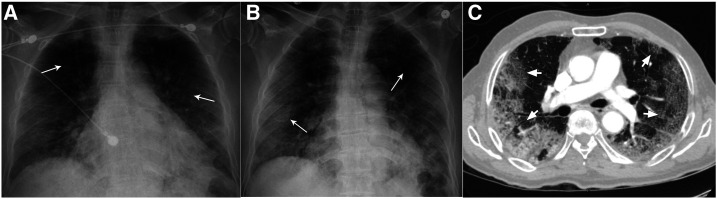

Figure 1.

Chest radiography. (A) Chest X-ray on initial presentation showing bilateral peripheral patchy infiltrates (arrows). (B) Chest X-ray on readmission showing worsened bilateral peripheral patchy infiltrates (arrows). (C) Computed tomogram of the thorax showing peripheral-based extensive multi-lobar ground-glass opacities (arrows).

A 71-year-old man with no significant past medical history presented with 2 weeks of fever, cough, shortness of breath, and chest discomfort with coughing in early April 2020 at a tertiary care hospital in New Brunswick, NJ. He was exposed to his daughter who was diagnosed with COVID-19 pneumonia a week before he fell ill. On presentation, he was afebrile at 99.7°F (37.6°C), blood pressure was 134/67 mmHg, tachycardic with a pulse of 102/minute, tachypneic at 34 breaths/minute, and hypoxic at 78% breathing room air. Examination was notable for faint crackles over all lung fields. Supplemental oxygen via nasal cannula (NC) was initiated at 4 L/minute with improvement of saturation to 94%. Initial laboratory investigations revealed absolute lymphopenia and elevated D-dimer, lactate dehydrogenase (LDH), ferritin, and C-reactive protein (CRP) (Table 1). His chest X-ray showed peripheral bilateral patchy opacities (Figure 1A). A nasopharyngeal swab specimen tested positive for SARS-CoV-2 by reverse transcription–PCR. We started him on hydroxychloroquine therapy. By the third day, he was comfortable, only requiring supplemental oxygen on mobilization, and was discharged to a COVID-19 Federal Medical Station.

However, he was readmitted 2 days later with worsened hypoxia. Vitals revealed he was afebrile at 98.9°F (37.1°C), blood pressure was 134/80 mmHg, tachycardic with a pulse of 112/minute, tachypneic at 34 breaths/minute, and hypoxic to 88% on 4 L/minute of oxygen via NC. Examination still noted bilateral crackles in all lung fields. Repeat investigations revealed positive COVID-19 test, persistent absolute lymphopenia, and further elevation of D-dimer, LDH, ferritin, and CRP (Table 1). A repeat chest X-ray showed worsened bilateral patchy opacities (Figure 1B). Saturations improved to 92% on 6 L/minute of oxygen supplementation. Hydroxychloroquine therapy was discontinued because of elevated QTc of 505 milliseconds. With worsening COVID-19 pneumonia, we initiated methylprednisolone 40 mg intravenously twice daily, along with lopinavir–ritonavir 400–100 mg orally twice daily and enoxaparin 40 mg subcutaneously twice daily. A computed tomography–pulmonary angiogram was negative for pulmonary embolism (PE) but revealed extensive multi-lobar ground-glass opacities (Figure 1C). Because of persistent dyspnea and hypoxia in the next 2 days, he was intermittently proned while on 6 L/minute oxygen via NC, and maintained saturation of 90–92%. Laboratory parameters were repeated intermittently as noted in Table 1. On day #9 since initial presentation, the patient complained of sharp left iliac fossa and left flank pain, which was high grade (8/10), constant, and radiating to his back, associated with nausea but no vomiting, diarrhea, dysuria, hematuria, fever, chills, or rigors. Urinalysis revealed clear, straw-colored, non-bloody urine with 30 mg/dL protein. An urgent computed tomography angiogram (CTA) revealed left superior renal artery thrombi with infarcts in the posterior mid-pole of the left kidney (Figure 2A, C, and D). The CTA also revealed ascending aortic thrombus (Figure 2B). Bilateral lower extremity ultrasound was negative for deep venous thrombosis (DVT). We initiated heparin intravenous infusion for therapeutic anticoagulation and discontinued enoxaparin. A loading dose of clopidogrel 300 mg was given and continued with 75 mg daily. On surgical review, no intervention was advised. The next day, the abdominal pain had resolved, but we discontinued lopinavir–ritonavir as the hepatic enzymes were rising. The oxygen requirement decreased to 4 L/minute by day #12 since presentation, and we switched to apixaban 5 mg orally twice daily for anticoagulation. The patient continued to steadily recover, with improving inflammatory and renal markers (Table 1). The urine output and electrolytes remained normal throughout (Table 1). By day #14 since initial presentation, the patient was with a saturation of 90% on room air at rest, only requiring supplemental oxygen on mobilization, and corticosteroids were discontinued. The next day, he was discharged home with home oxygen therapy and 3 months of apixaban and clopidogrel regimen.